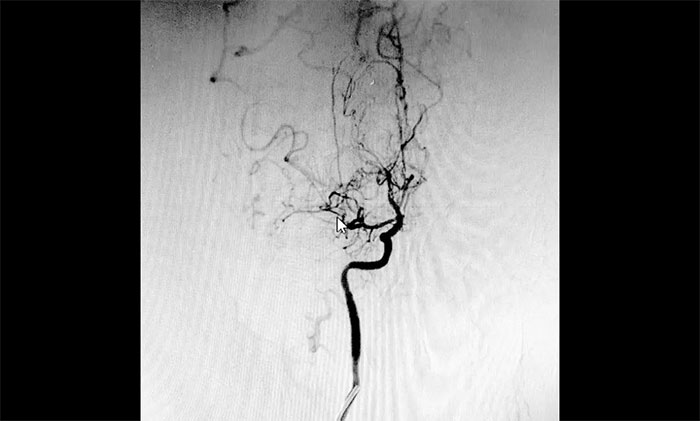

剛?cè)朐旱姆断壬庾R狀態(tài)時(shí)好時(shí)壞,人非常消瘦,精神萎靡。神經(jīng)外科于耀宇主任團(tuán)隊(duì)第一時(shí)間為其完善相關(guān)檢查,DSA檢查顯示,患者雙側(cè)頸內(nèi)動脈纖細(xì),雙側(cè)大腦前、中動脈主干節(jié)段性狹窄,中遠(yuǎn)端分支明顯減少,局部見代償性異常血管網(wǎng),符合煙霧病特征。

▲ 異常血管網(wǎng)形似“煙霧”

結(jié)合患者的影像檢查報(bào)告,于耀宇主任團(tuán)隊(duì)針對病情和治療方案展開審慎的討論和評估,一致商定患者雙側(cè)大腦半球多發(fā)供血區(qū)灌注不足,左側(cè)額葉部腦出血已過急性期,異常小血管仍可能反復(fù)破裂出血,應(yīng)盡快通過血運(yùn)重建手術(shù),改善顱內(nèi)血供、改善灌注、預(yù)防缺血性及出血性卒中二次發(fā)生的風(fēng)險(xiǎn)。